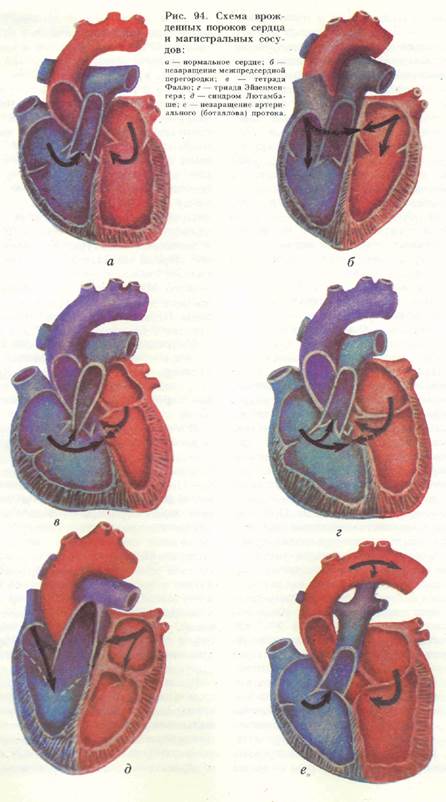

Фотографии и информация о приобретенных пороках сердца